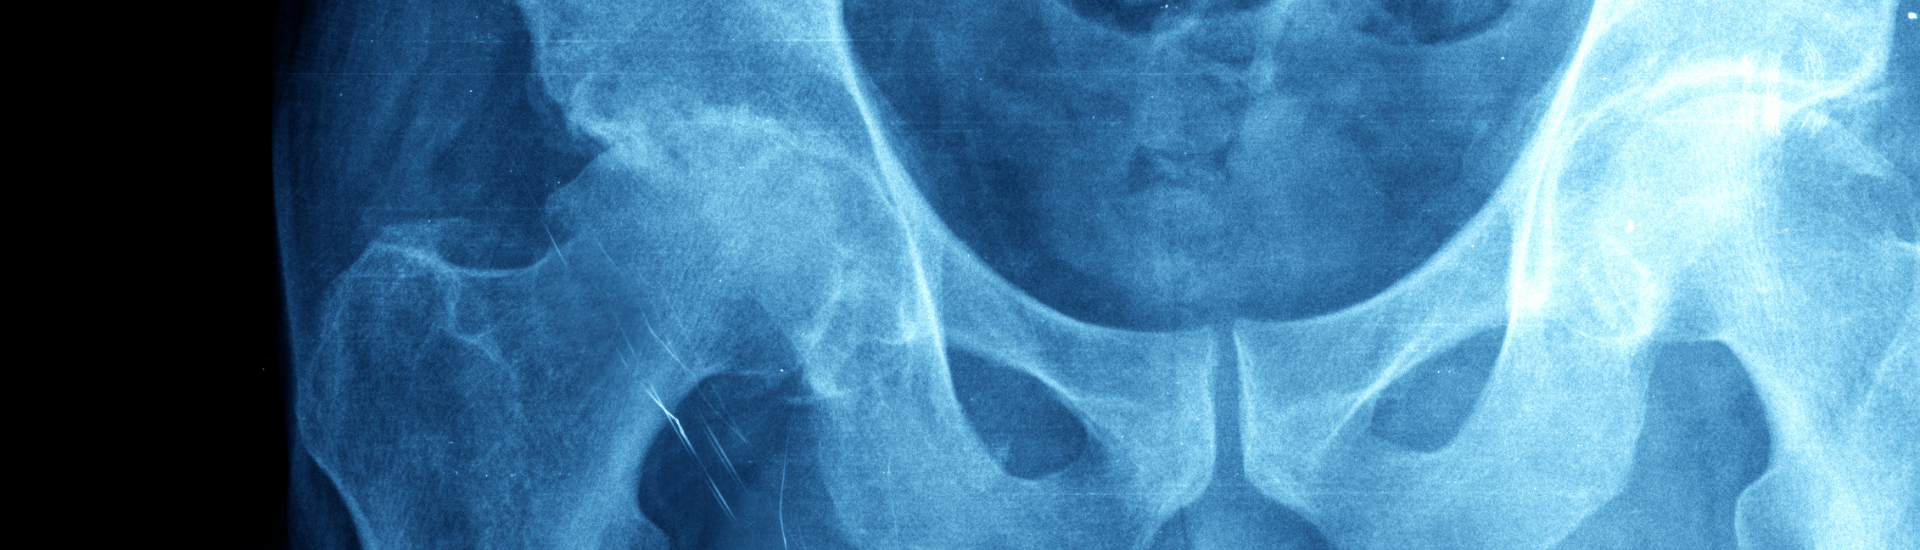

L’RX Apparato Urinario è un esame radiologico che permette di visualizzare dettagliatamente l’anatomia e la funzionalità dell’apparato urinario. Presso il Poliambulatorio S-Medical Group di Sora, questo esame è condotto da esperti, garantendo risultati precisi e affidabili.

Utilizzando raggi X, l’RX Apparato Urinario ottiene immagini dettagliate dell’apparato urinario. Questa tecnologia innovativa consente ai medici di valutare la struttura e il funzionamento dei reni, ureteri e vescica. Nel Poliambulatorio S-Medical Group di Sora, i pazienti beneficiano di apparecchiature all’avanguardia e di un team di professionisti altamente qualificati, pronti a eseguire questo esame con massima cura.

Questo esame diagnostico riveste un’importanza cruciale nella diagnosi e valutazione delle condizioni che interessano l’apparato urinario. Attraverso le immagini fornite dall’RX, i medici possono identificare calcoli renali, tumori, infezioni e altre anomalie che potrebbero compromettere la salute delle vie urinarie. Le informazioni ottenute sono vitali per formulare diagnosi accurate e pianificare il trattamento più adeguato.

Grazie a questo esame, è possibile ottenere immagini chiare delle strutture e dei dettagli dell’apparato urinario. Le immagini fornite consentono di valutare la forma e le dimensioni dei reni, la presenza di calcoli renali o ostruzioni, e anomalie strutturali. Queste informazioni sono cruciali per una diagnosi precisa e per la pianificazione di un trattamento efficace.